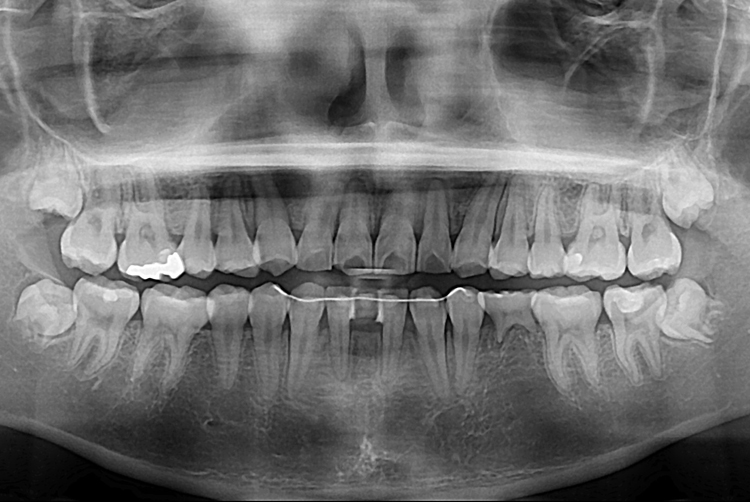

[임플란트] 앞니 임플란트

치료후 : 2019-07-31

세종치과는 많은 환자와 다양한 케이스를 바탕으로

항상 편안한 임플란트 수술을 제공하고자 노력하고,

오래동안 튼튼히 쓸 수 있는 임플란트 수술을 가장 큰 목표로 삼고 있습니다.